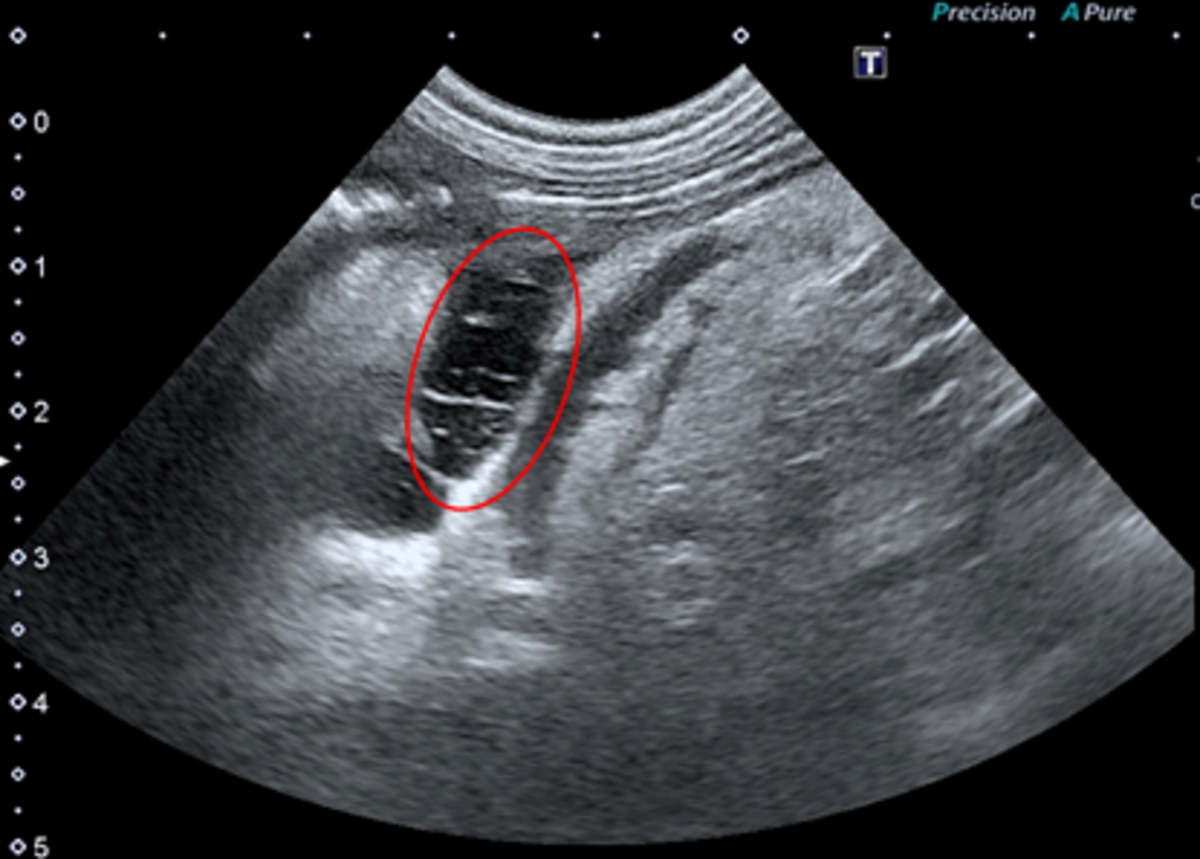

まず、身体検査を実施しました(表2)。本人の状態はそれほど悪そうではありませんでした。血液検査はかかりつけ医で既に実施されていましたが、来院時の状態を確認するために超音波検査と血液検査を実施しました。超音波検査では、膵臓周囲に限局的な液体貯留が確認されました。網嚢内(脾静脈の被膜下)に液体が溜まっており(図1)、膀胱周囲や腎臓周囲に腹水はなく、急性膵炎に特徴的な病態が確認できました。

図1 膵左葉の超音波検査(赤丸:網嚢内に見られた液体貯留)